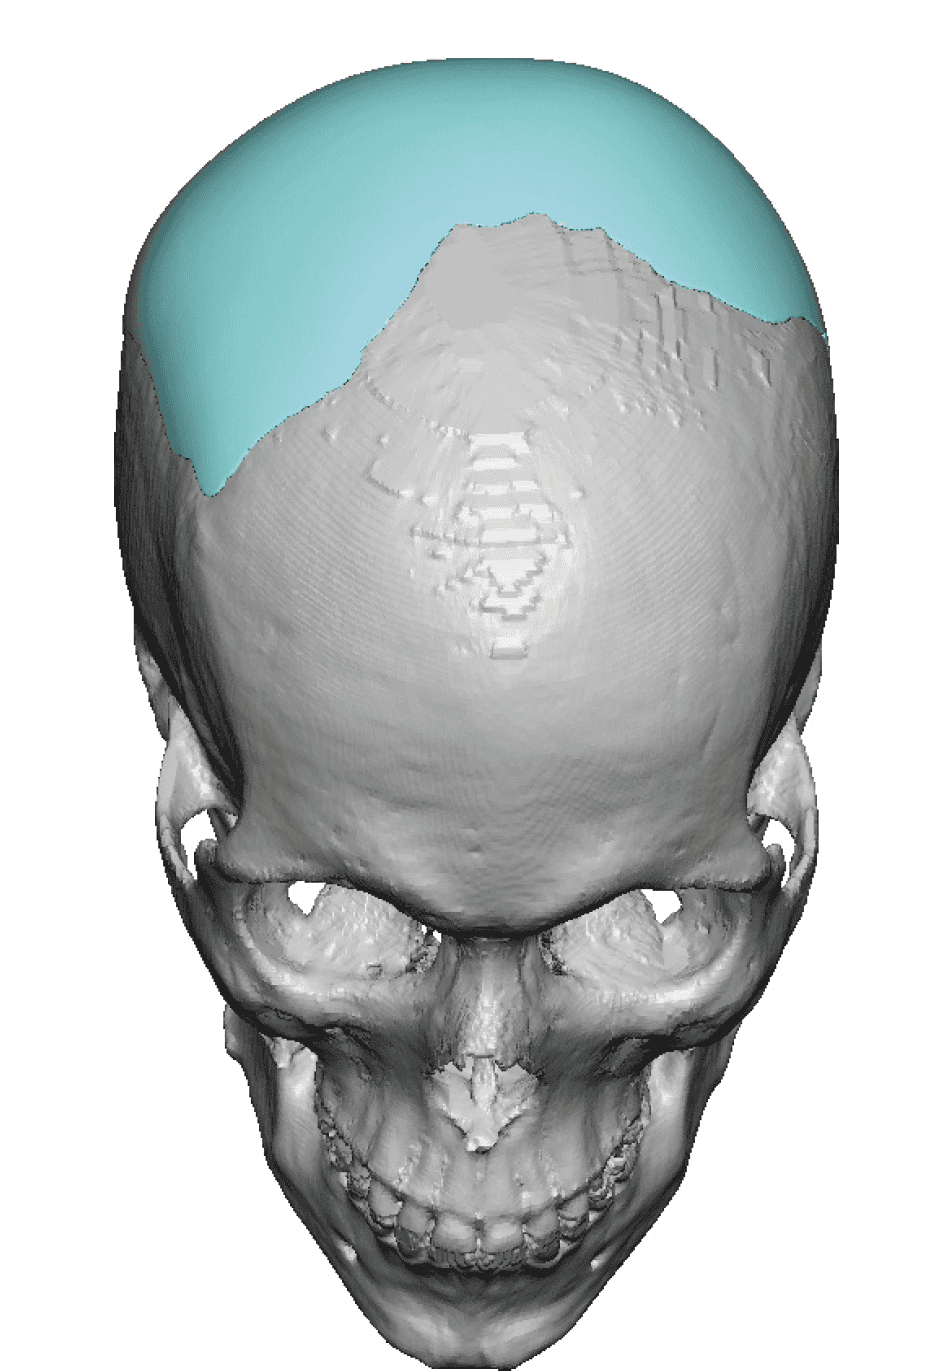

Severe narrowing skull deformity from prior sagittal craniosynostosis repair as an adult.

Complete replacement of entire skull by a custom implant with temporal fat injections.

Severe narrowing skull deformity from prior sagittal craniosynostosis repair as an adult.

Complete replacement of entire skull by a custom implant with temporal fat injections.